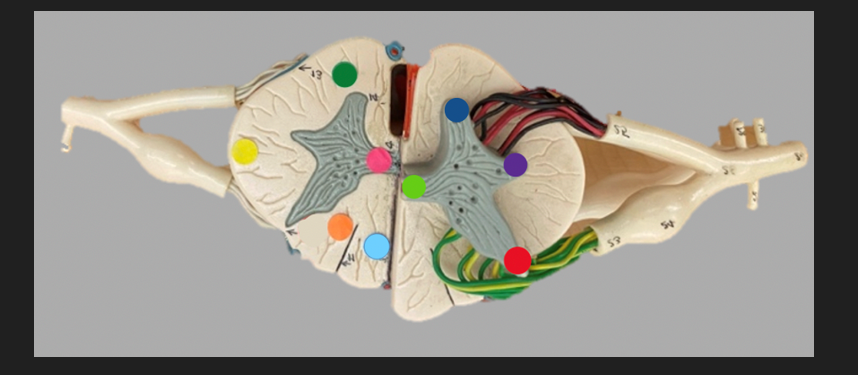

green dot

spinal nerve

orange dot

ventral root

pink dot

dorsal root

blue dot

dorsal root ganglion

red dot

dorsal ramus

yellow dot

ventral ramus

purple dot

anterior median fissure

red dot

posterior (dorsal) horn

purple dot

lateral horn

dark blue dot

anterior (ventral) horn

orange dot

dorsal column

yellow dot

lateral column

dark green

anterior column

line green and pink doit

gray commissure

light blue dot

posterior median sulcus